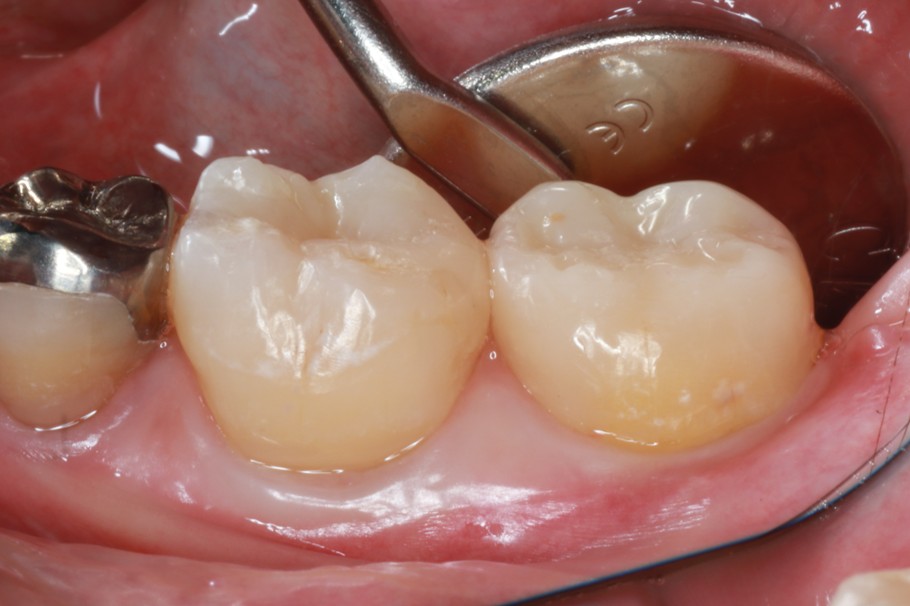

症例2

| 患者様データ | 40代 男性 |

| 来院時の主訴 | 「左下が痛くて噛めない。」 |

| 医院の診断 | 左下第一大臼歯歯根破折、慢性根尖性歯周炎 |

| 治療費 | 総額:275,000円(税抜) 【内訳】 歯牙移植150,000円、ファイバーポストコア20,000円、セラミック治療85,000円、歯頸部ダイレクトボンディング10,000円×2 |

| リスクと副作用 | ①根管治療歯は長期的には破折するリスク ②長期的なメインテナンスが必要 ③歯根の外部吸収 |

抜歯が必要になった際に余っている親知らずがあれば移植歯として利用することができます。 術前に撮影したCT画像から3Dプリンターを用いて親知らずのレプリカを作製することで、親知らずが乾燥することを防ぎ、成功率が上がるよう努力しています。 |